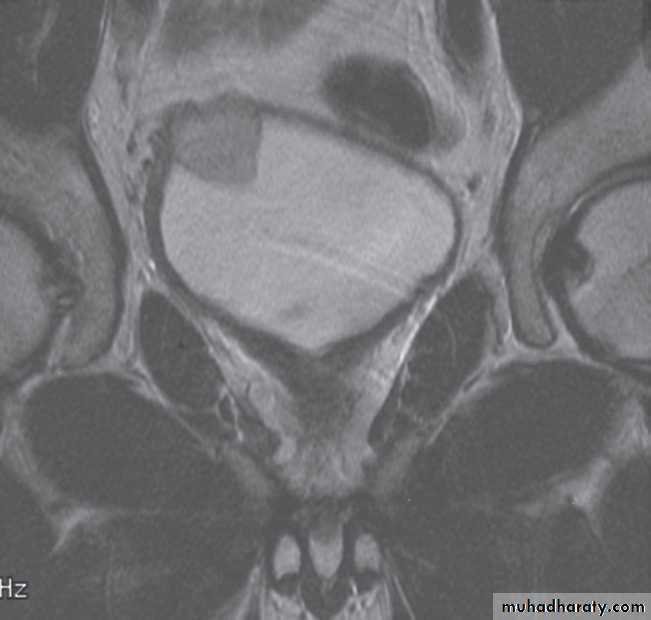

Magnetic resonance imaging is best imaging modality for staging , used to assess early stage prostate cancer in patients being considered for radical surgery or radiotherapy. Tumour in the peripheral zone is seen as a relatively low signal mass within the normal high signal of the peripheral zone on T2-weighted images.

MRI is used to demonstrate extracapsular tumour spread, to show invasion of the seminal vesicles, and to demonstrate possible lymph

node metastases .